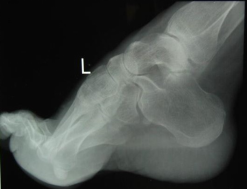

先天性马蹄内翻足

手足短骨解剖及常见疾病的影像学表现